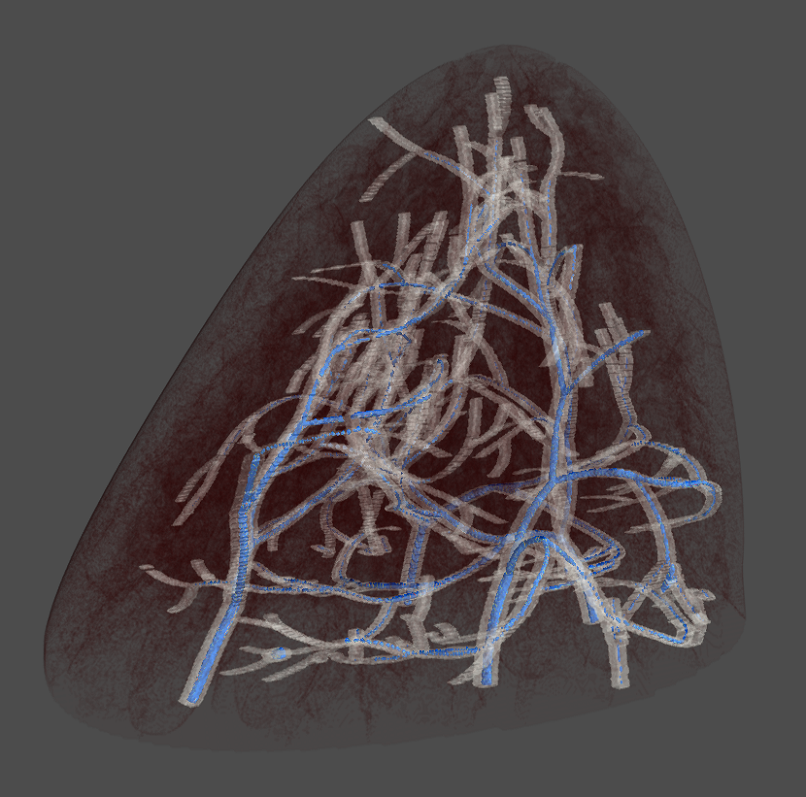

Our method is based on the theory of persistent homology [20], which extracts 1D (loops) and 2D (bubbles) topological structures with guaranteed robustness [14]. These structures correspond to curvilinear tissue structures (e.g., ducts, vessels, etc.) and voids enclosed by tissues and glands in their proximity. As shown in Fig. 2, compared to previous radiomics features, the topological structures provide a much richer structural context for the modeling of tumor microenvironment. Since these structures are extracted in an unsupervised manner, the quality of their interpretation becomes a key consideration. Using a phantom breast imaging dataset (VICTRE [5]), we validate both quantitatively and qualitatively that these topological structures are reasonable approximations of the breast tissue structures. As illustrated in Fig. 1, the extracted topological structures delineate the glandular tissues of a phantom breast image.

2.2 Persistence Cycles and Their Computation

Although the persistence diagram has been used for topological analysis in various dataset [27, 74, 78], it only records limited information, i.e., the times at which these topological structures appear/disappear. We hypothesize that a detailed geometric realization of these topological structures can be crucial for learning from images. To this end, we propose extracting these topological structures and integrating them into the learning process. As shown in Fig. 3, we extract loops (blue) to denote 1D topological structures and bubbles (red) for 2D topological structures. These structures are then used to guide the attention mechanism within the neural network.

Upon selecting topological structures based on persistence, we use the voxels from their representative cycles to craft topological masks. We generate two distinct binary 3D masks that represent the 1D and 2D topological cycles. Empirical observations have revealed that a ”soft” mask conveys more detailed information. Rather than directly employing binary masks, the foreground voxels are populated with their inherent image intensity values. Given that all masked MRIs are padded to a size of , we subsequently produce two topological masks, and , which pertain to the 1D and 2D topological cycles, respectively.

Qualitative validation. Figure 6 illustrates how topological structures effectively capture breast tissues. The first row presents 3D renderings of VICTRE-generated synthetic breast phantoms for four distinct profiles. The second and third rows display two slices at different positions of the corresponding breast phantoms, where the topological mask (in blue) and ground truth breast tissues (in white) are shown, alongside the breast outlines (in red). It is important to note that each slice’s rendering includes several additional slices around the target cross sections for detailed examination. It is clear that the blue topological structures closely match the white breast tissues, especially noticeable in the scattered and fatty volumes. This observation highlights that our extracted topological masks effectively mirror the actual breast tissues, confirming the biological significance of these structures.